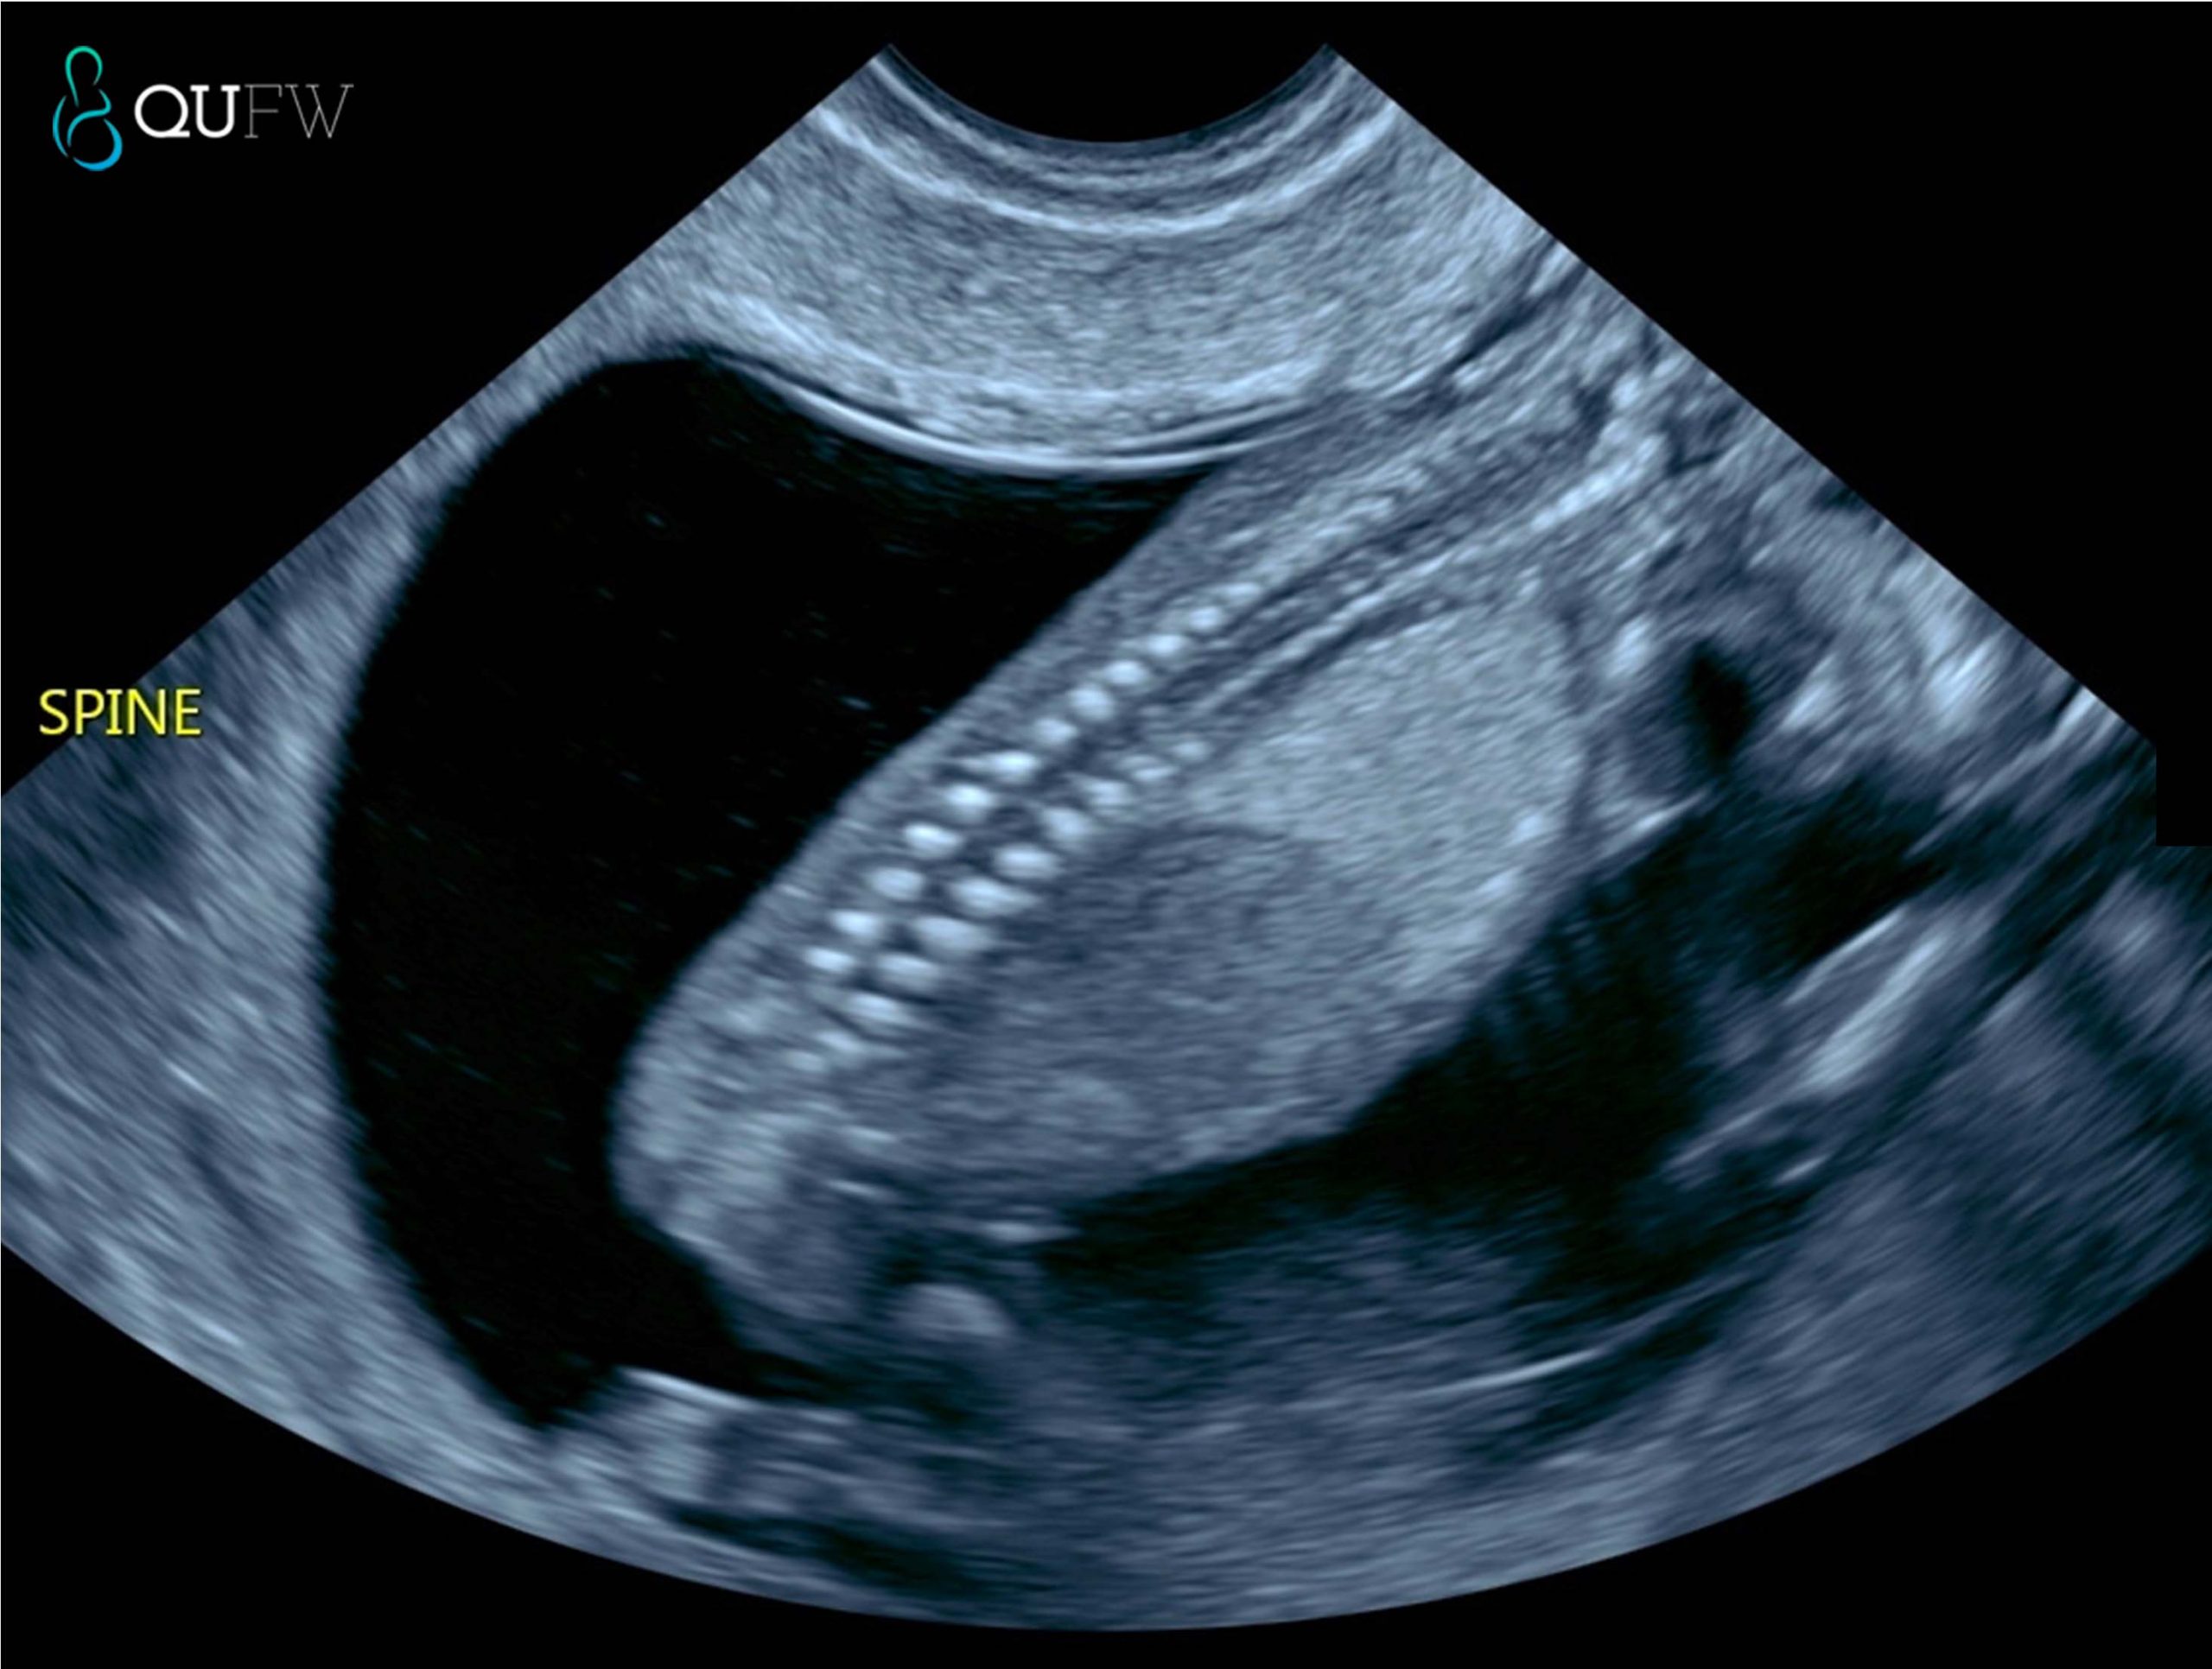

- Spine and intact overlying skin

Early structural assessment of the spine